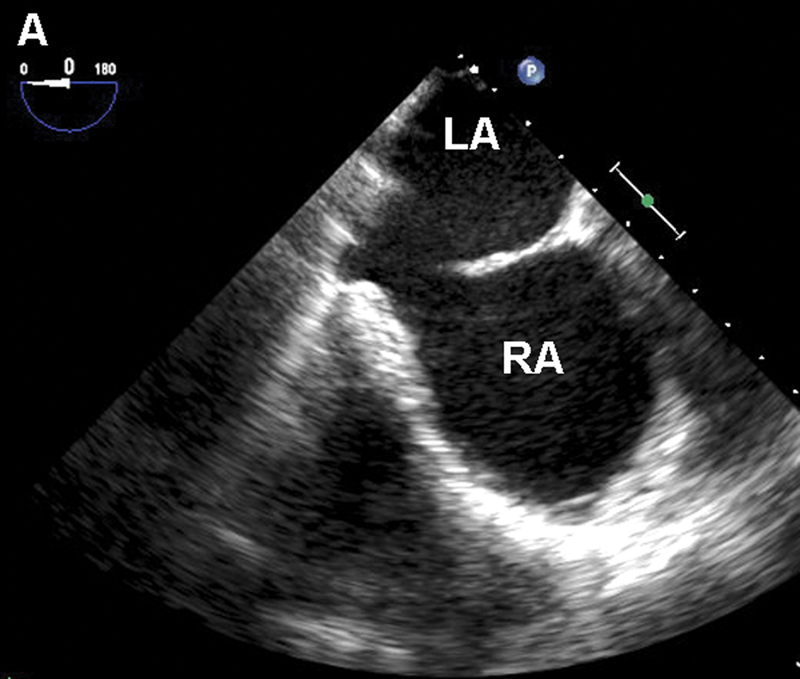

فحوصات تشخيصية لبعض امراض القلب والشرايين التاجية